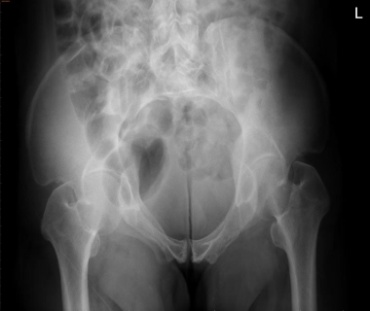

术后影像

经过术中、术后影像学检查确认,骨折复位良好,内固定位置满意。手术仅留下几个1-2厘米左右的小切口,术中出血约100ml,术后48小时患者即可在床上自主活动,现恢复良好。